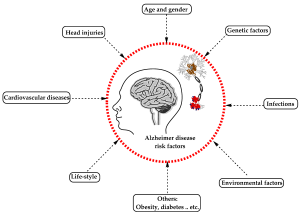

بررسی کامل عوامل خطر آلزایمر: آیا جنسیت و دیگر عوامل نقش دارند؟

عوامل موثر در بروز آلزایمر: چه چیزهایی خطر ابتلا را افزایش میدهد؟